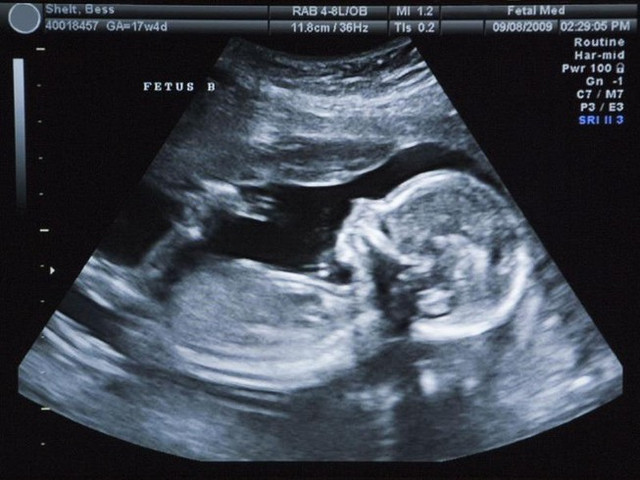

Bệnh nhi đuợc bệnh viện Từ Dũ chuyển bệnh viện Nhi đồng 2 (TP.HCM). Tại đâu, các bác sĩ ghi nhận khối choán chỗ lớn trong ổ bụng thai nhi, bên trong có cấu trúc dịch, mô mỡ, và nhiều cấu trúc dạng xương ống và xương dẹt, nhiều mạch máu. Do khối u quá to gây tình trạng suy hô hấp nên các bác sĩ chỉ định phẫu thuật cấp cứu cho bé.

Trong lúc phẫu thuật, các bác sĩ bệnh viện Nhi đồng 2 ghi nhận khối u chiếm gần hết ổ bụng, nằm phía dưới gan, mạch máu nuôi xuất phát từ mạch máu dạ dày, u có dạng bào thai, với cấu trúc túi chứa dịch nằm cạnh khối này tương tự túi ối, cùng với nhiều cấu trúc xương trưởng thành như xương vai và xương ống, xương cột sống không hoàn chỉnh lắm, tuy nhiên hình dạng các chi trưởng thành khá rõ.